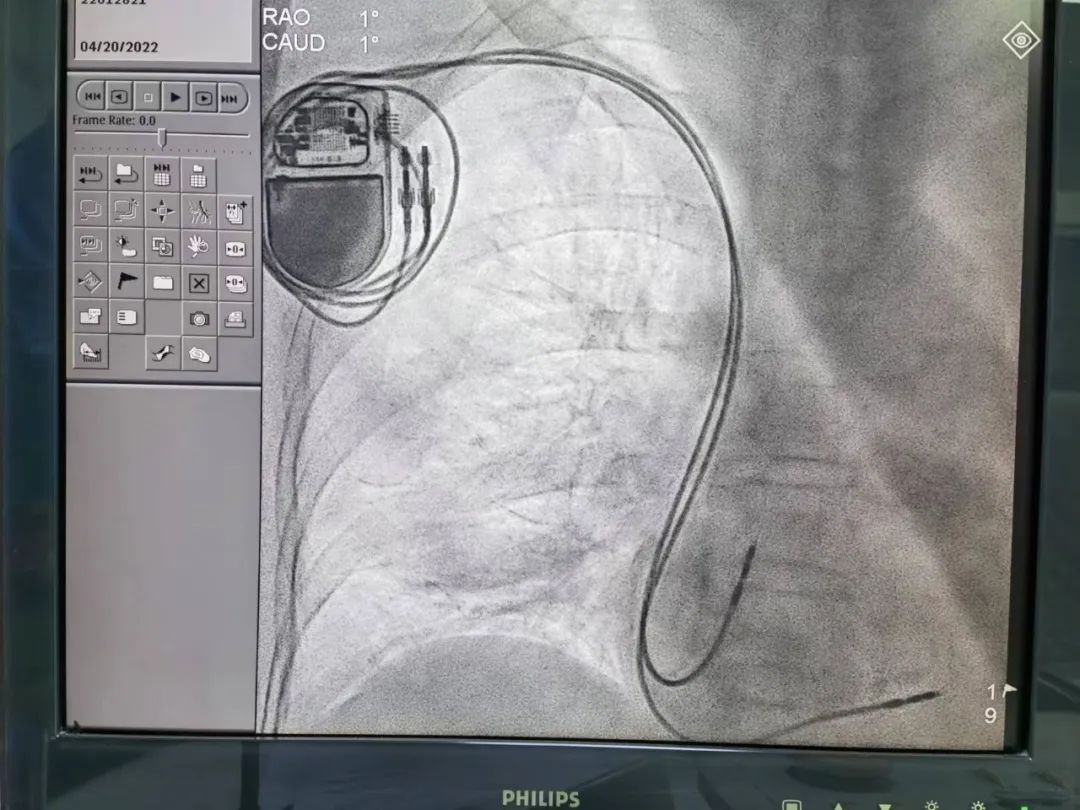

本次为患者植入的进口百多力双腔抗核磁(3.0)起搏器,是医院首个植入“集采”价格的抗核磁起搏器,集采前价格为75000元,根据最新医保政策现为37277元,降幅达50%;手术所需的两根电极导线单价也从8600元降至4819元,降幅达44%。